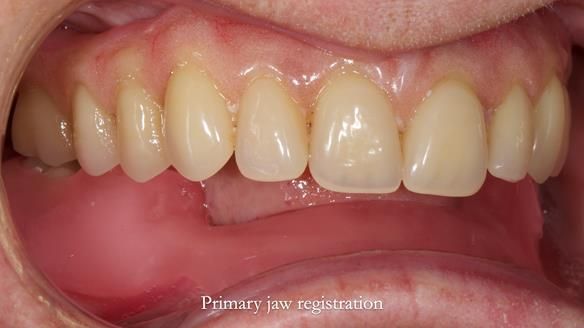

However, once Rowan and I reviewed the remaining metal crown on tooth 46, we realised it would make an ideal abutment for a gasket denture. By reshaping the lingual surface of the crown, we created an excellent gasket seal.

This approach worked far better than the proposed ring-clasp design - improving retention, comfort, and aesthetics while keeping the design clean and simple.

- The gasket seal around 46 was made using retention.sil 200, producing a precise, cushioned fit.